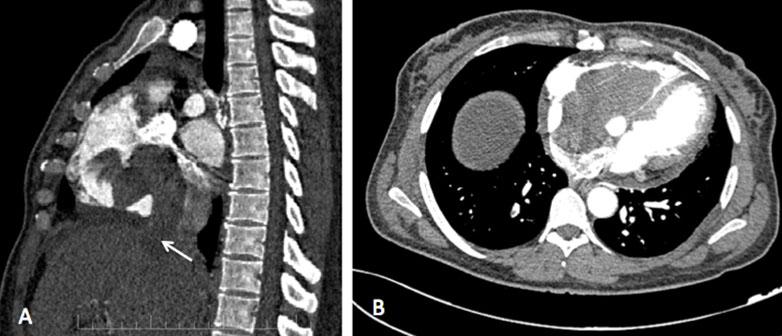

A 59-year-old woman, G0P0 diagnosed with an endometrial carcinoma FIGO stage III in good general condition. The patient underwent a contrast-enhanced abdominal CT showing an expanded right ovarian vein low-attenuation intraluminal material (Figure 1) presumably representing the thrombus. The thrombosis was reaching the inferior vena cava (IVC) and extending to the right atrium and ventricle (Figure 2). Diagnosis of venous thrombosis was highly suspected on the CT based on three criteria: venous enlargement, low-density intraluminal material, and a sharply defined enhancing wall.

Figure 1: Contrast-enhanced computed tomography, showing an enlarged heterogeneous right ovarian vein with central hypodense filling defect suggestive of thrombus (arrow). Note that the ovarian vein is as large as the contiguous inferior vena cava immediately to its left.